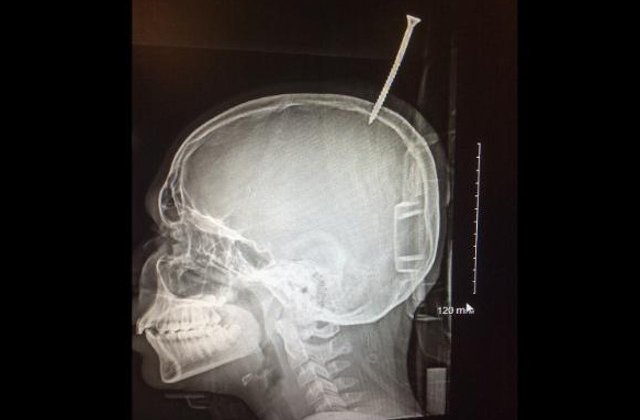

Baiatul lucra la constructia casutei din copac in momentul in care a cazut de pe ramura si a lovit o placa de lemn de un metru si jumatate.

Rama a picat peste el, iar un surub de 15 centimetri i-a perforat craniul, a declarat Joy Ellingsworth, mama lui Darius Foreman.

A fost nevoie de interventia pompierilor pentru a taia placa si a-l transporta pe baiat la spital. Medicii au constatat ca surubul nu a afectat nicio parte a creierului, astfel ca Darius a fost operat de urgenta.

"Cativa milimetri si ar fi sangerat pana la moarte. Am stat ca pe ace. Placa aceea a fost infipta in craniul copilului timp de sapte ore", a declarat neurochirurgul care l-a operat pe baiat, Alan Cohen, de la spitalul John Hopkins.